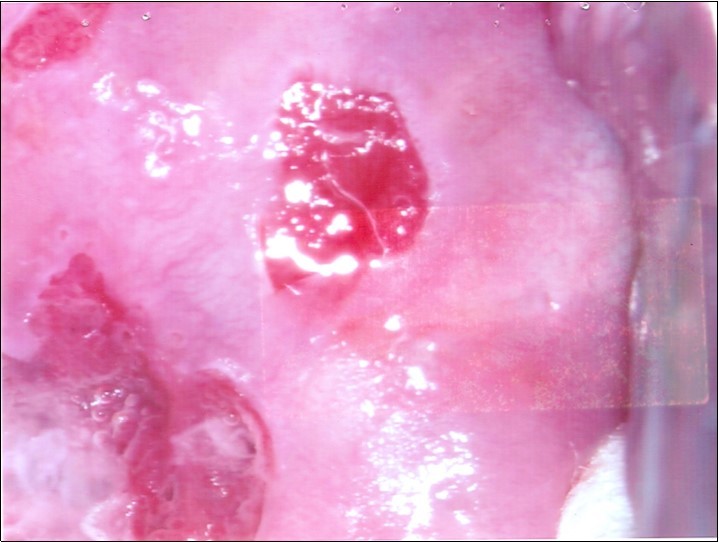

Repeat colposcopy was performed after 6 weeks. This revealed a small ulcerated area at the site of previous biopsy with rolled healing edges, and a separate small ulcer at the 12 o’clock position. (Figure 2a, Figure 2b, Figure 2c) Careful inspection of the buccal mucosa revealed similar ulcers in the left buccal region. (Figure 3)

Figure 2b.Repeat colposcopy (high magnification)